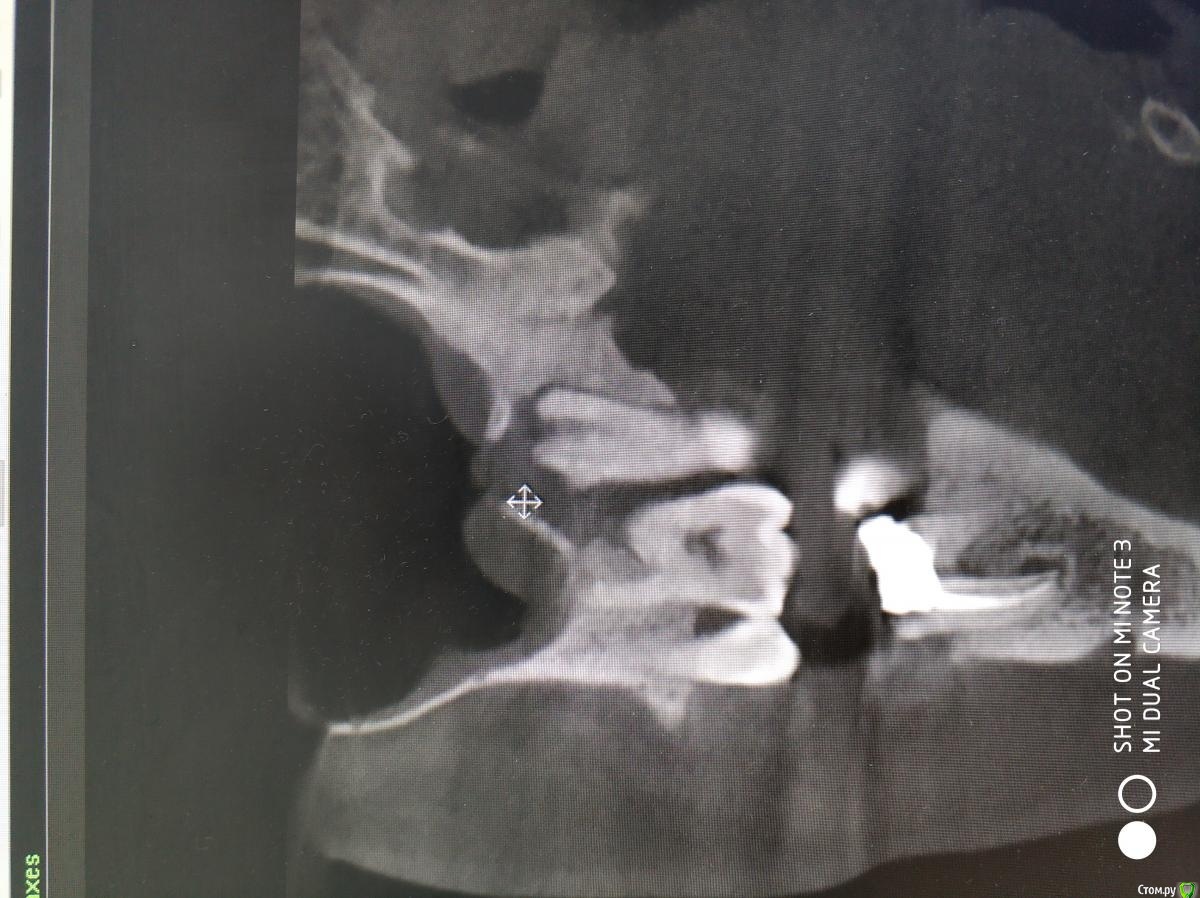

It'sGeorgy Опубликовано 20 февраля, 2021 Поделиться Опубликовано 20 февраля, 2021 А что именно смущает? Что дефект с пазухой сообщается? Так закроете после удаления, ничего страшного. ЛОРу, имхо, там делать нечего пока еще.Недавно был подобный случай: А вообще, судя по тем скринам, которые вы выложили, я бы пациента терапевтам показал для начала. Ссылка на комментарий

Raystom Опубликовано 20 февраля, 2021 Автор Поделиться Опубликовано 20 февраля, 2021 А что именно смущает? Что дефект с пазухой сообщается? Так закроете после удаления, ничего страшного. ЛОРу, имхо, там делать нечего пока еще.Недавно был подобный случай:12.png23.png22.png А вообще, судя по тем скринам, которые вы выложили, я бы пациента терапевтам показал для начала.Именно, что с пазухой. С терапевтами общались, при попытке препарирования зуб "мягкий", как кариозный судя по их словам Ссылка на комментарий